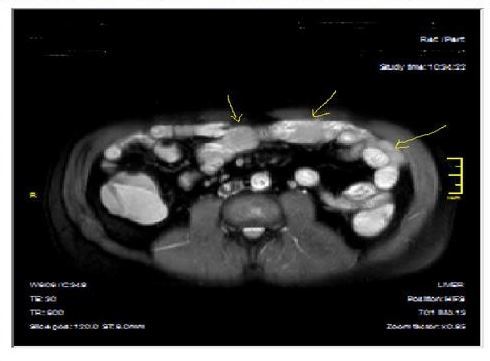

Figure 4a.Mucosal involvement and lack of opacified ileal segments with loss of intestinal folds and increased bowel wall thickness due to Crohn’s disease on T2W coronal sequence after OCA, presented at 37 years old male with moderate Crohn’s disease.

Figure 4b.Mucosal, luminal and bowel wall involvement in Crohn’s disease with skipped lesions, seen at T2W axial image after OCA, presented at 45 years old male with severe inflammatory disease.